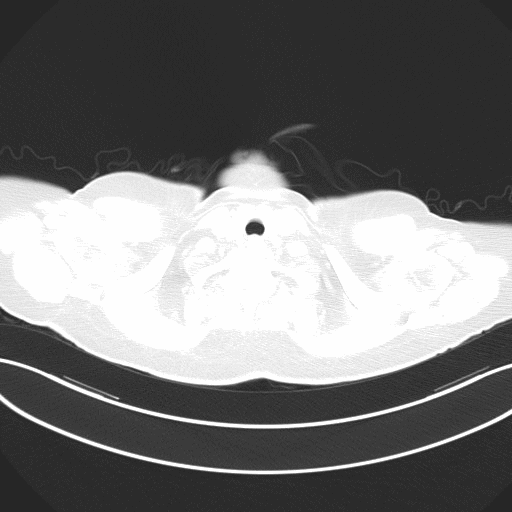

附图2 患者入院后24h胸部CT(2021-06-13)

双上肺部分小叶间隔增厚,双肺可见纹理增粗,渗出及胸膜增厚基本吸收